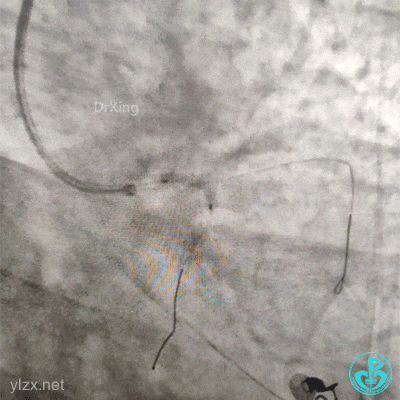

交换导丝后扩支架网眼。

结束手术。

下台时血压127/78mmHg,心率75次/分。